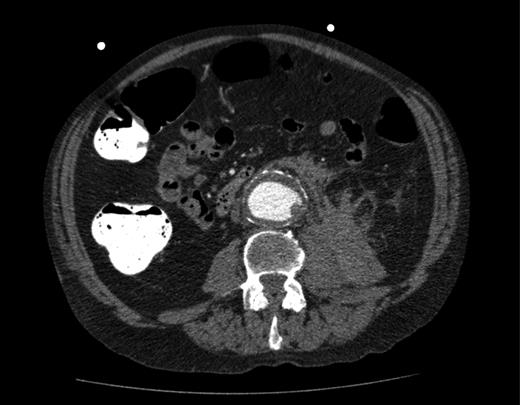

A computed tomography (CT) of the abdomen and pelvis was performed. This showed a grossly distended urinary bladder and compression of the sigmoid colon against the sacral promontory causing bowel obstruction (Figs 1 and 2, respectively) as well as a 4.9 cm abdominal aortic aneurysm without any signs of a rupture (Fig. 3). The plan was to consult our vascular colleagues regarding management of the AAA once the obstruction had settled.

The initial CT scan of the abdomen showing a large distended bladder.